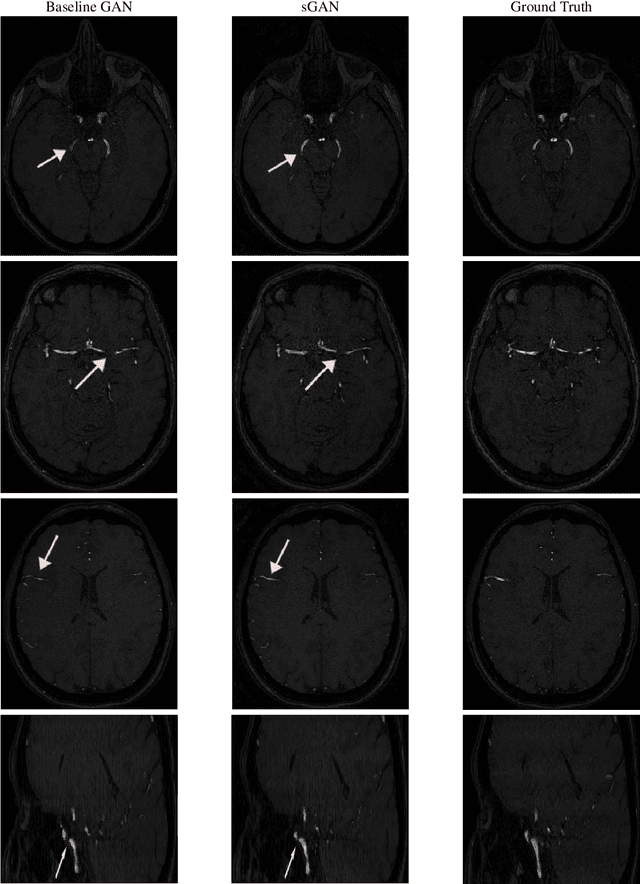

Abstract:Magnetic Resonance Angiography (MRA) has become an essential MR contrast for imaging and evaluation of vascular anatomy and related diseases. MRA acquisitions are typically ordered for vascular interventions, whereas in typical scenarios, MRA sequences can be absent in the patient scans. This motivates the need for a technique that generates inexistent MRA from existing MR multi-contrast, which could be a valuable tool in retrospective subject evaluations and imaging studies. In this paper, we present a generative adversarial network (GAN) based technique to generate MRA from T1-weighted and T2-weighted MRI images, for the first time to our knowledge. To better model the representation of vessels which the MRA inherently highlights, we design a loss term dedicated to a faithful reproduction of vascularities. To that end, we incorporate steerable filter responses of the generated and reference images inside a Huber function loss term. Extending the well- established generator-discriminator architecture based on the recent PatchGAN model with the addition of steerable filter loss, the proposed steerable GAN (sGAN) method is evaluated on the large public database IXI. Experimental results show that the sGAN outperforms the baseline GAN method in terms of an overlap score with similar PSNR values, while it leads to improved visual perceptual quality.